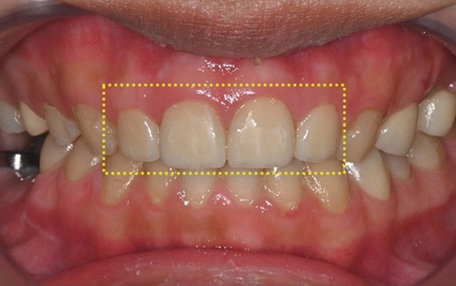

Why upper molar implants can be difficult

If a tooth has been missing for a long time,

or if dentures have been used for an extended period,

or naturally as we age,

as the jawbone gradually resorbs,

the amount of bone height needed to place an implant

may become insufficient.

If an implant is placed immediately in this state,

the fixation may be weak,

and over time it can lead to wobbling or discomfort.

That is why, for upper molar implants,

we first check the bone condition

and, if necessary, consider a sinus lift together.